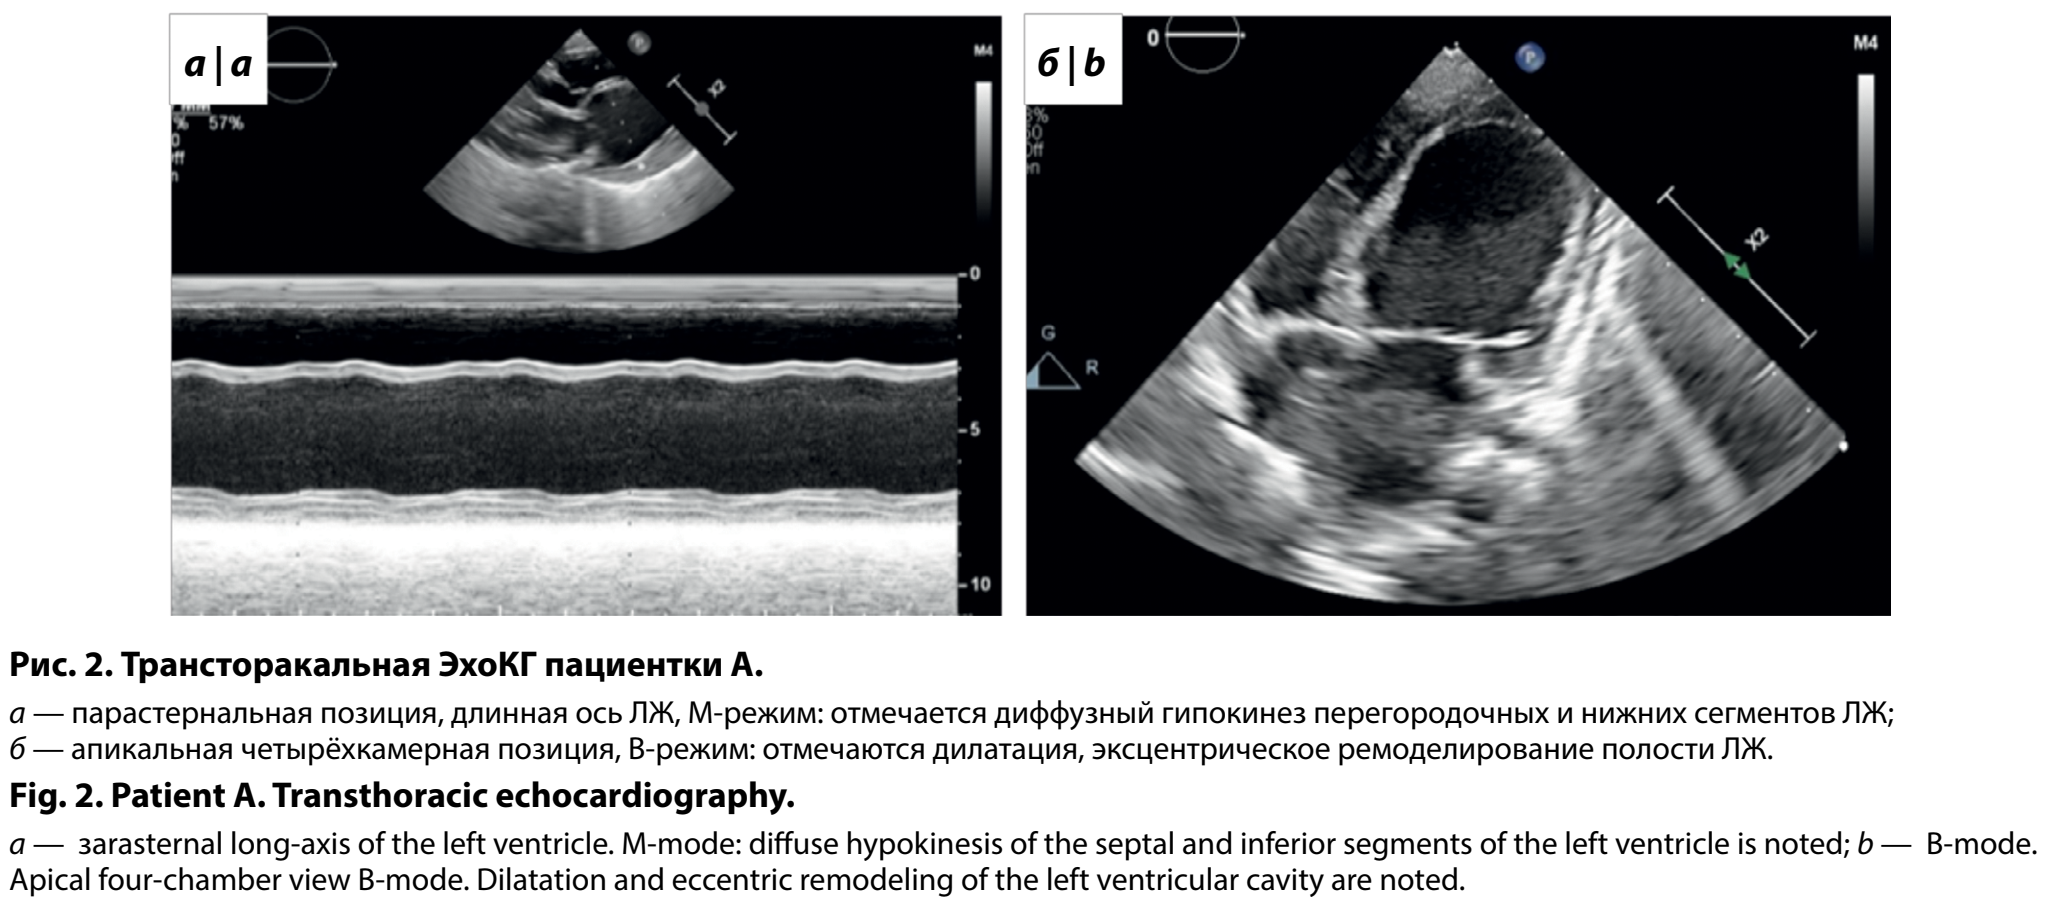

В 15 мес девочка впервые госпитализирована в кардиологическое отделение Центра по системе телемедицины. При поступлении обращало на себя внимание низкое, дисгармоничное физическое развитие (вес 8,3 кг, рост 74 см), диффузная мышечная гипотония. По результатам обследования сохранялся высокий уровень NTproBNP — 2889 пг/мл, отмечалось снижение параметра креатинфосфокиназы до 11 ЕД/л. По данным ЭхоКГ отмечена дилатация ЛЖ до 3,6 z-score и ЛП до 4,2 z-score, снижение ФВ до 13% по Симпсон, давление в системе лёгочной артерии составило 50 мм рт. ст., выявлены признаки некомпактного миокарда ЛЖ (рис. 2). По результатам рентгенографии органов грудной клетки кардиоторакальный индекс составил 71%. При проведении ЭКГ-исследования, включая СМ-ЭКГ, значимых нарушений ритма сердца и проводимости не регистрировалось. За период пребывания в отделении девочке была скорректирована медикаментозная терапия сердечной недостаточности. При контрольном плановом обследовании состояния через 6 мес получены следующие данные: уровень NTproBNP 2469 пг/мл; сохранялись эхо-признаки ремоделирования по дилатационному фенотипу без значимого изменения параметров; нормализовалось давление в системе лёгочной артерии; уменьшились рентгенологические размеры сердца (кардиоторакальный индекс 69%); по данным СМ-ЭКГ обращали на себя внимание эпизоды синусовой тахикардии без эктопической активности. Терапия была скорректирована в соответствии с результатами обследования.